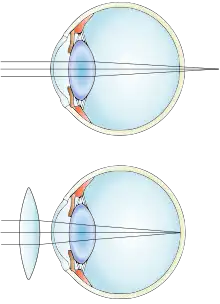

| Far-sightedness without (top) and with lens correction (bottom) | |

Far-sightedness, also known as long-sightedness, hypermetropia, and hyperopia, is a condition of the eye where distant objects are seen clearly but near objects appear blurred. This blur is due to incoming light being focused behind, instead of on, the retina due to insufficient accommodation by the lens.[6] Minor hypermetropia in young patients is usually corrected by their accommodation, without any defects in vision.[2] But, due to this accommodative effort for distant vision, people may complain of eye strain during prolonged reading.[2][7] If the hypermetropia is high, there will be defective vision for both distance and near.[2] People may also experience accommodative dysfunction, binocular dysfunction, amblyopia, and strabismus.[3] Newborns are almost invariably hypermetropic, but it gradually decreases as the newborn gets older.[6]

The simplest form of treatment for far-sightedness is the use of corrective lenses, i.e. eyeglasses or contact lenses.[16][17] Eyeglasses used to correct far-sightedness have convex lenses.[18]